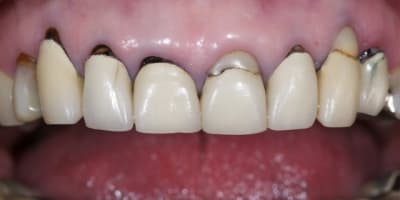

La demande concerne la réhabilitation esthétique du bloc incisif supérieur.

On ne parlera pas de bruxisme, de dvo, de gouttière et de réhabilitation globale pour diverses raisons, seule le traitement esthétique de 14 a 24 nous concerne ici et ses différentes solutions pour le traiter.

Alors j'ai commencé le traitement:

-ext 24 car mobilité type 2 + implant immédiat + couronne prov. en sous occ.

-Démontage difficile des ccm, mais surprise, traitement endo relativement mou et donc a priori pas trop délicat a reprendre.

-couronnes prov.